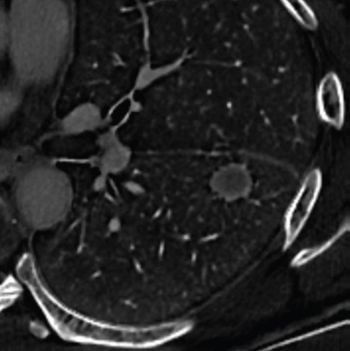

Researchers showed that adjunctive use of a deep learning algorithm resulted in an eight percent increase in sensitivity and a nearly 10 percent increase in specificity for differentiating between colon carcinoma and acute diverticulitis on computed tomography (CT) scans.